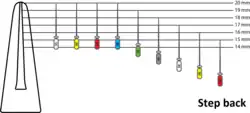

There have been a number of progressive iterations to the mechanical preparation of the root canal for endodontic therapy. The first, referred to as the standardized technique, was developed by Ingle in 1961, and had disadvantages such as the potential for loss of working length and inadvertent ledging, zipping or perforation.[12][13] Subsequent refinements have been numerous, and are usually described as techniques. These include the step-back, circumferential filing, incremental, anticurvature filing, step-down, double flare, crown-down-pressureless, balanced force, canal master, apical box, progressive enlargement, modified double flare, passive stepback, alternated rotary motions, and apical patency techniques.[14]

The step back technique, also known as telescopic or serial root canal preparation, is divided in two phases: in the first, the working length is established and then the apical part of the canal is delicately shaped since a size 25 K-file reaches the working length; in the second, the remaining canal is prepared with manual or rotating instrumentation.[15] This procedure, however, has some disadvantages, such as the potential for inadvertent apical transportation. Incorrect instrumentation length can occur, which can be addressed by the modified step back. Obstructing debris can be dealt with by the passive step back technique.[16] The crown down is a procedure in which the dentist prepares the canal beginning from the coronal part after exploring the patency of the whole canal with the master apical file.

An example of step back technique

An example of step back technique -